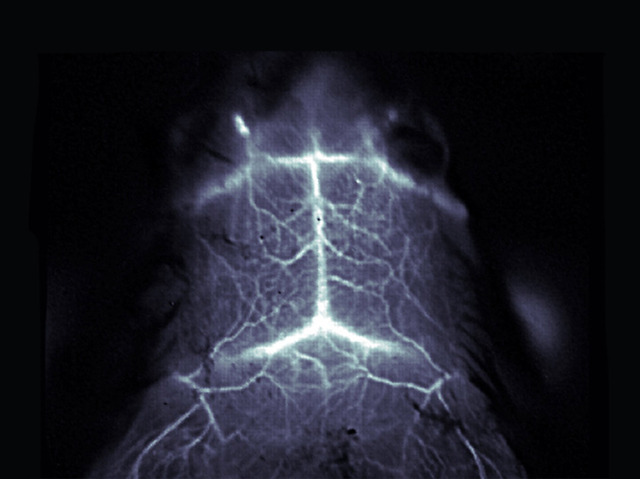

Glowing Health

Changes to blood circulation in the brain can be a symptom of migraine, a stroke or even Alzheimer’s but can’t easily be seen with X-rays or magnetic resonance scanning. Sharper and more detailed 3D images – and even video sequences – can be obtained by scanning with near infrared light, although a major drawback is that only a few millimetres of surface tissue can be penetrated. To get around this problem, scientists injected a mouse with carbon nanotubes, which fluoresce strongly in near infrared light, before scanning its brain. This experiment produced high quality images of blood vessels near the surface of the brain, like the one shown here, without the need to remove part of the animal’s skull. The technique will aid research on animals into brain diseases and could in theory be used for diagnosis in humans, although proof would be required that the procedure is safe.